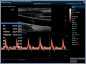

Neben einem ausführlichen Gespräch, der Anamnese, Zeit und Zuwendung gehören auch die Anwendung von wissenschaftlich evaulierten diagnostischen Verfahren zu einer guten Eingangsuntersuchung. Ich freue mich Ihnen in meiner Praxis deshalb nun auch die Ultraschalluntersuchung mit modernster Technik, einem mindray Consona N6 anbieten zu können.

- Darstellung der Schilddrüse - Darstellung der hirnversorgenden Gefäße mit Messung der Intimadicke (IMD) - Ultraschall des Herzens z. B. Stenose / Dichtigkeit der Herzklappen, Wandbewegungsstörungen,... - Ultraschall des Bauchraumes wie Leber, Gallenblase, Nieren, Blase, Milz. - Gefäßdarstellung

Video Farbdoppler der Halsarterie zur Darstellung der Durchblutung Video Farbdoppler der Niere zur Darstellung der Durchblutung Video Herzultraschall eines gesundes Herzens mit guter Pumpfunktion Video Herzultraschall mit eingeschränkter Pumpfunktion und vergrößerten Vorhöfen Video Herzultraschall bei Herzinsuffizienz und undichter Herzklappe